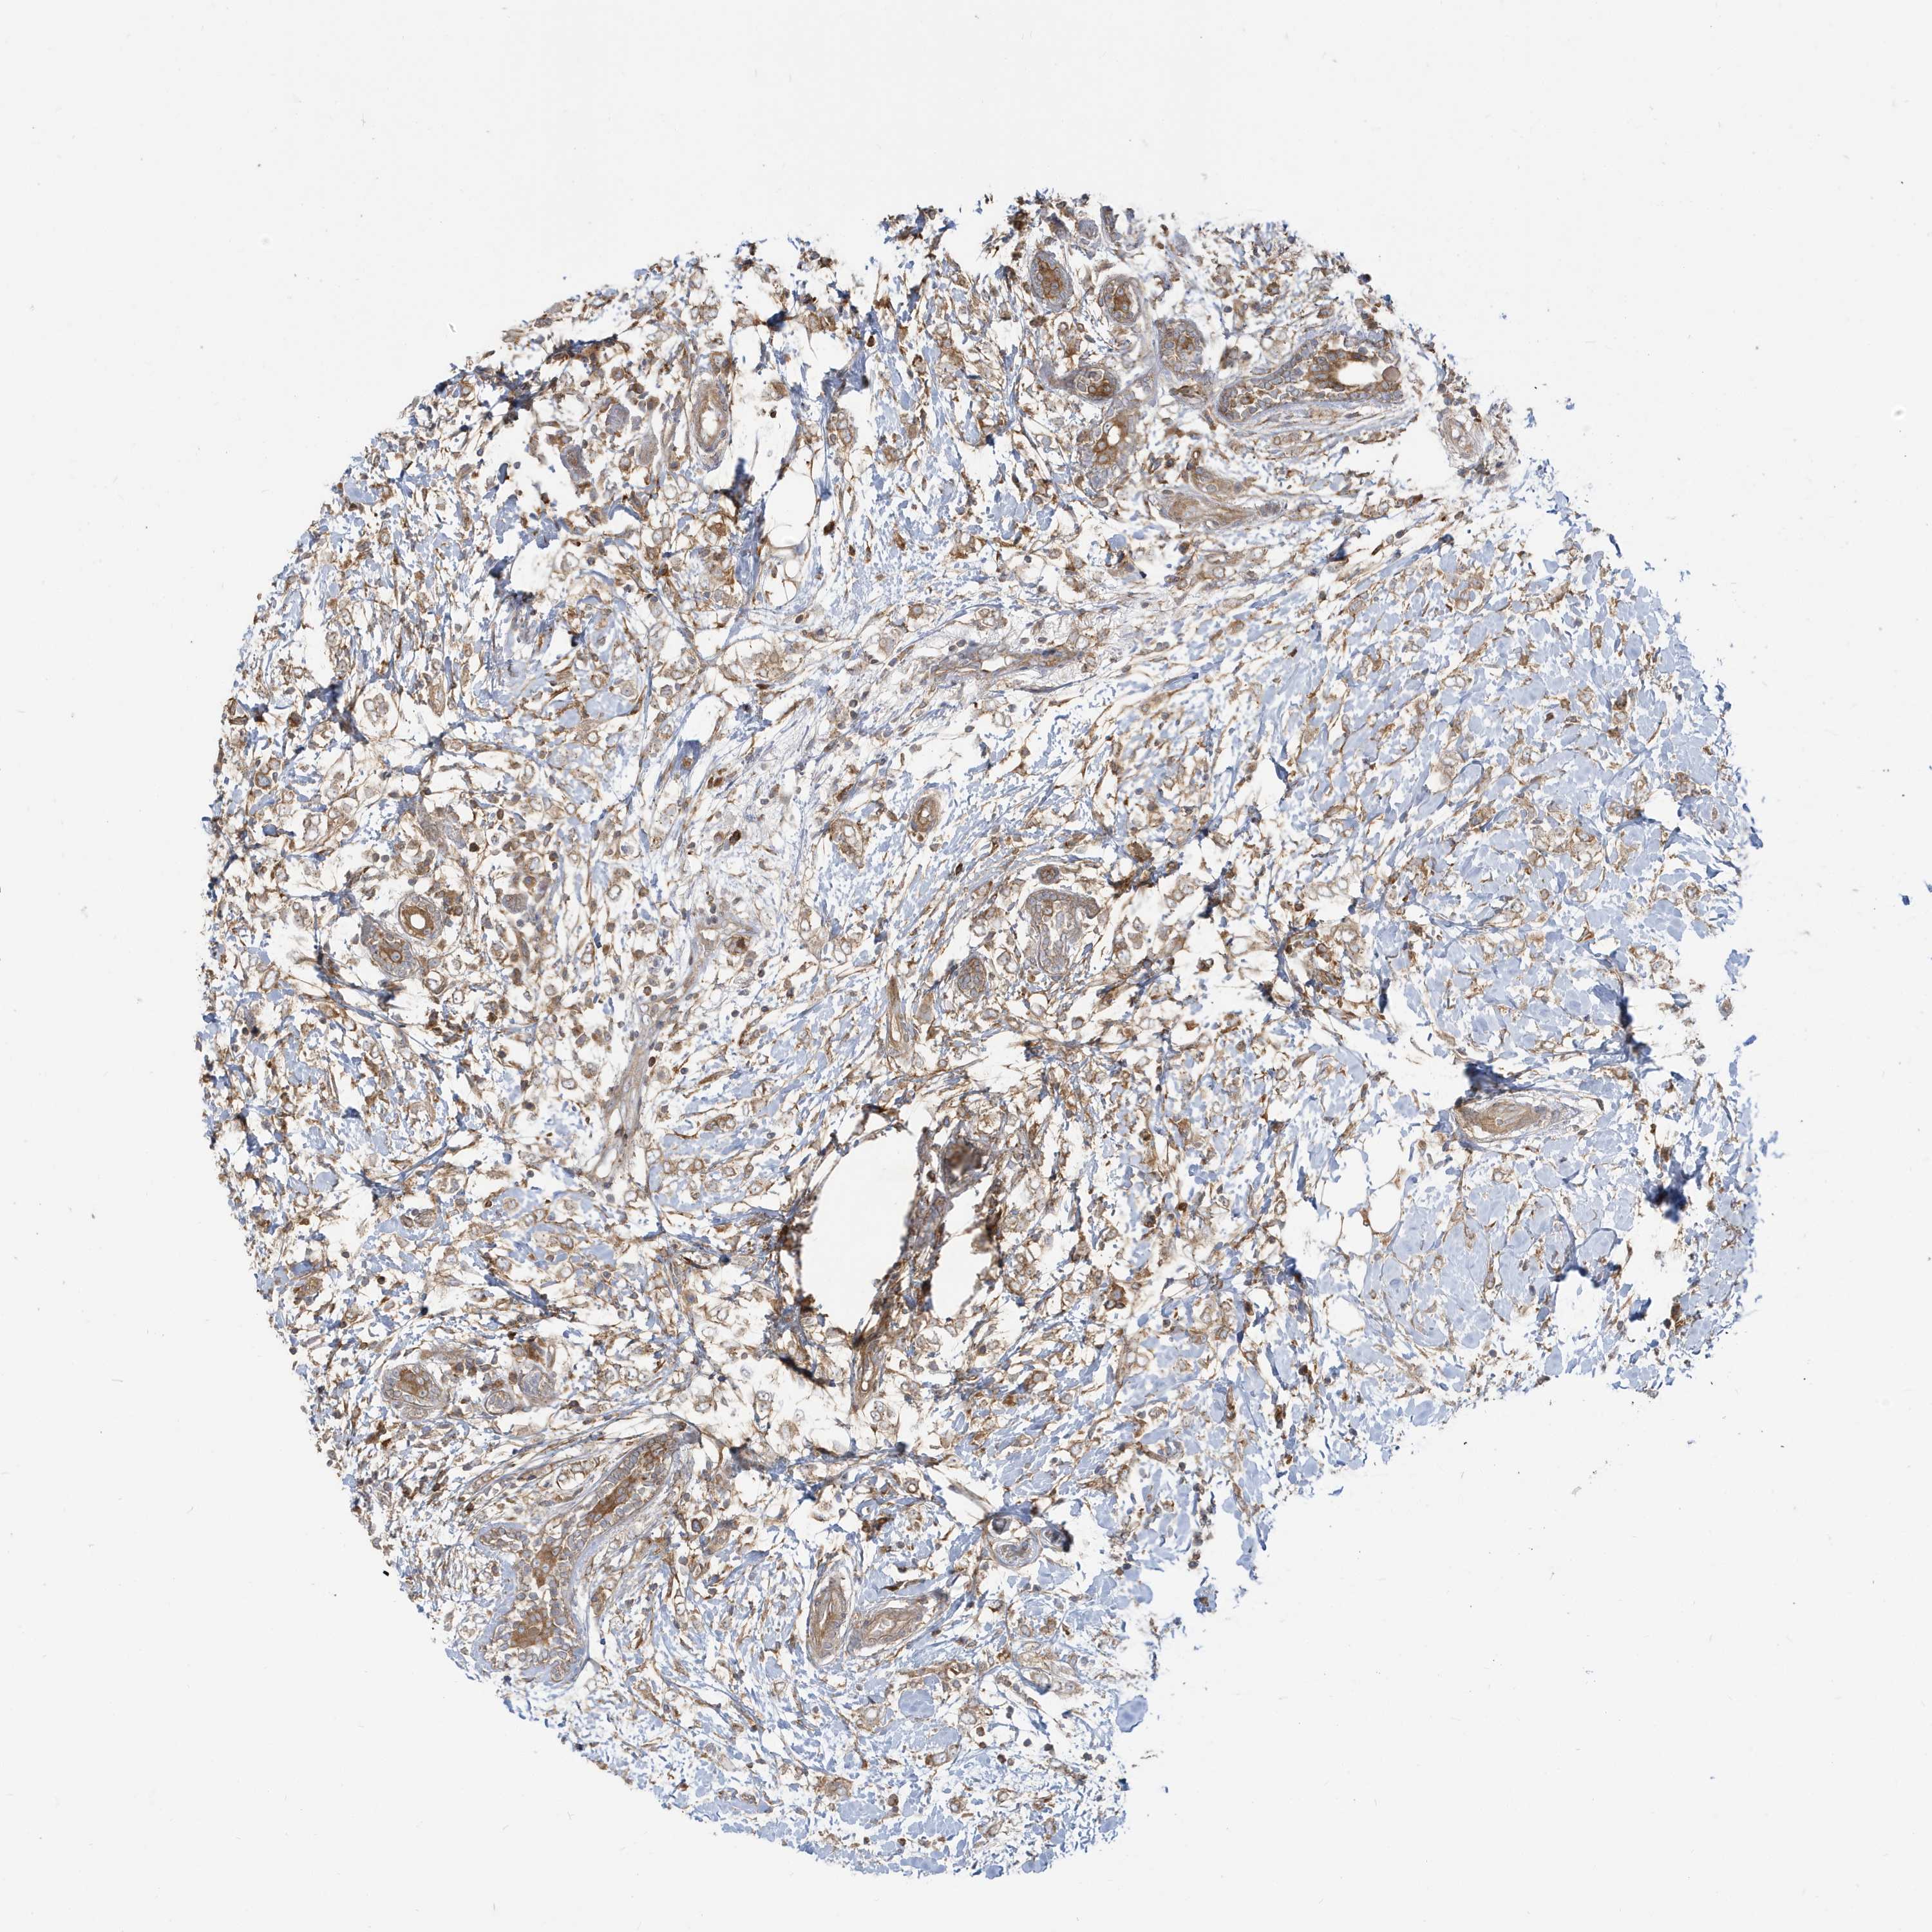

CANCER BREAST CANCER Show tissue menu

BRCA TCGA BRCA VALIDATION PROTEIN EXPRESSION